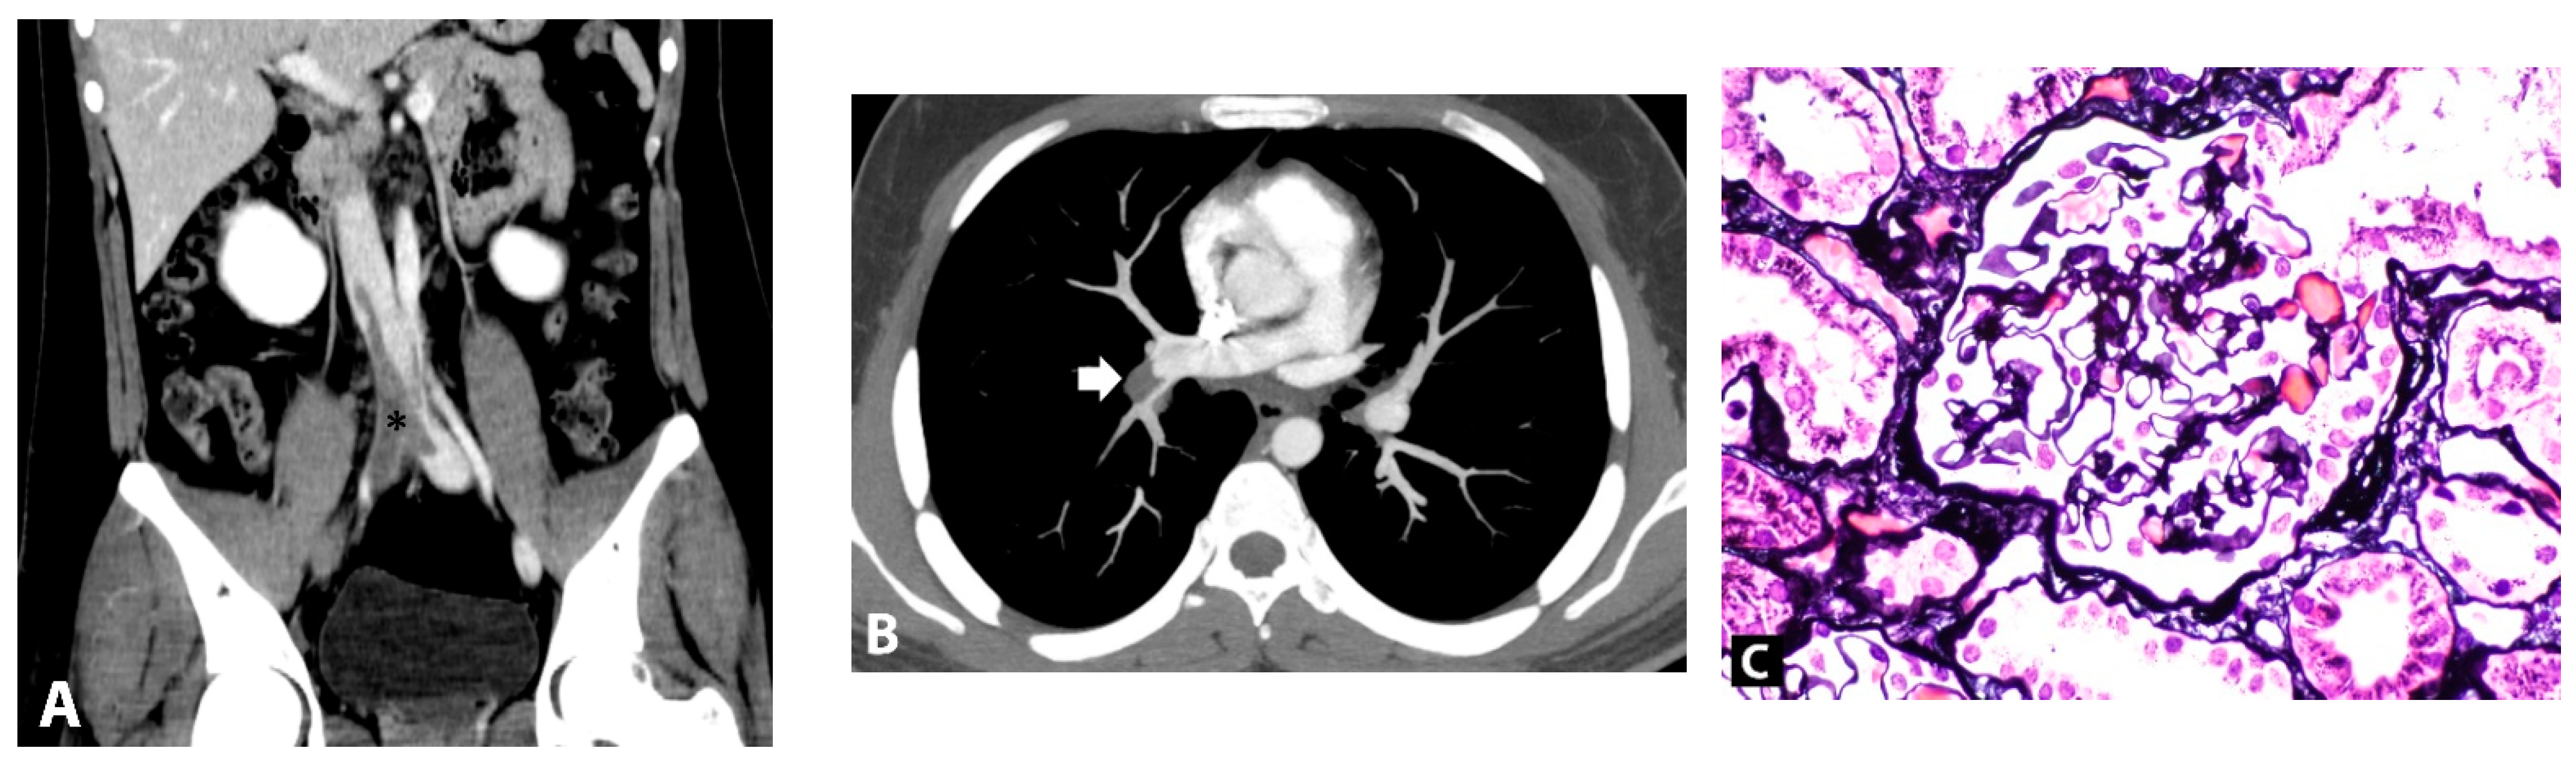

2. Case Presentation